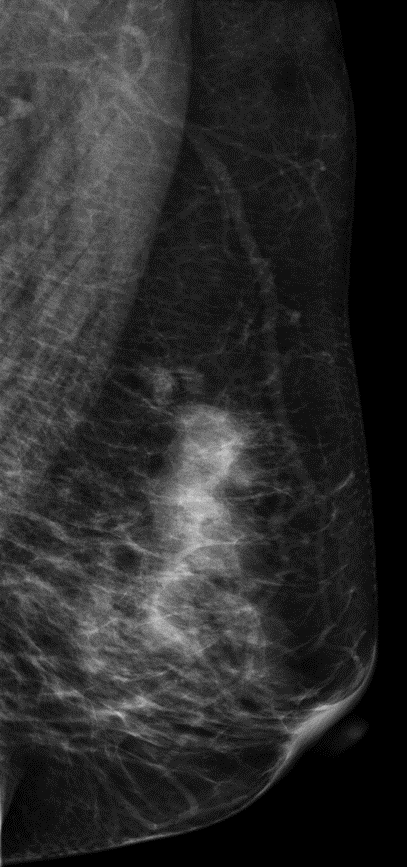

患者,52岁,发现肿物3个月。

常规2D和V-Preview图像左乳外上象限可到一不规则形团块影,呈分叶状,肿块的部分界限不清,在DBT图像上我们可以清楚观察到肿块的大小范围及边缘呈细小毛刺样改变。

左乳肿物 。     BI-RADS 4C级

DBT图像对观察肿块大小、范围及周边情况显示清晰,可以给我们诊断提供了更多影像诊断信息。